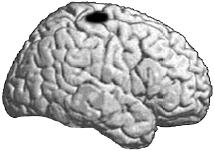

1.1. Гиппокамп — парный орган, расположенный в медиальных височных отделах полушарий головного мозга. Слева показан гиппокамп в разрезе (секущая плоскость изображена на рисунке посередине). Справа — продольный разрез.